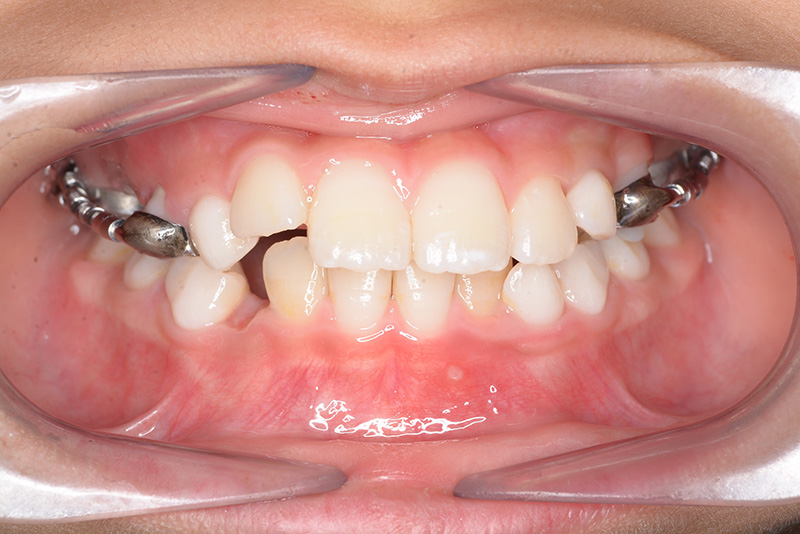

| 口腔内所見 | over jet 2.5mm、over bite 2.0mm、右側大臼歯関係はEnd on class Ⅱ、上顎左側Eは早期喪失により左側大臼歯関係はFull classⅡ、右側Eは6の異所萌出により歯根吸収が進行したため一般歯科医院にて抜去済みであった。 |

| 批評・予后 | 早期に6の遠心移動を行いナンスのホールディングアーチにて保隙をした結果、5は良好な状態で萌出できたように思う。 今後は永久歯列完成まで経過観察を行っていく予定である。 |